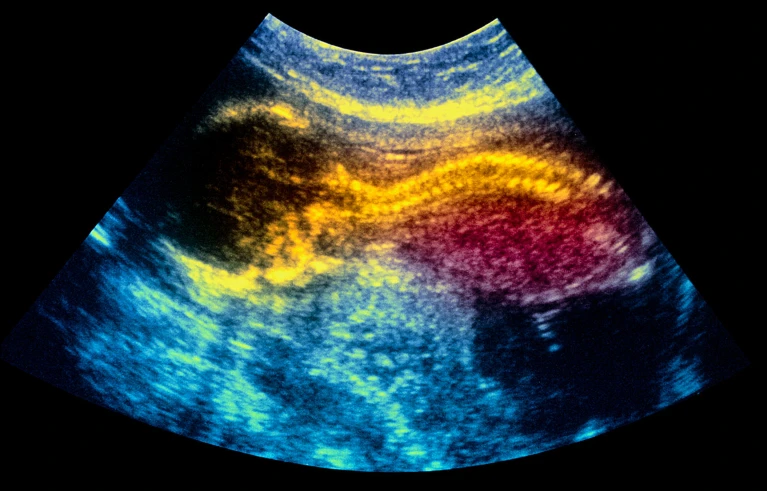

一种利用胎盘来源干细胞的宫内治疗技术,有望治愈患有脊柱裂的胎儿。图片来源:Fraser/Science Photo Library